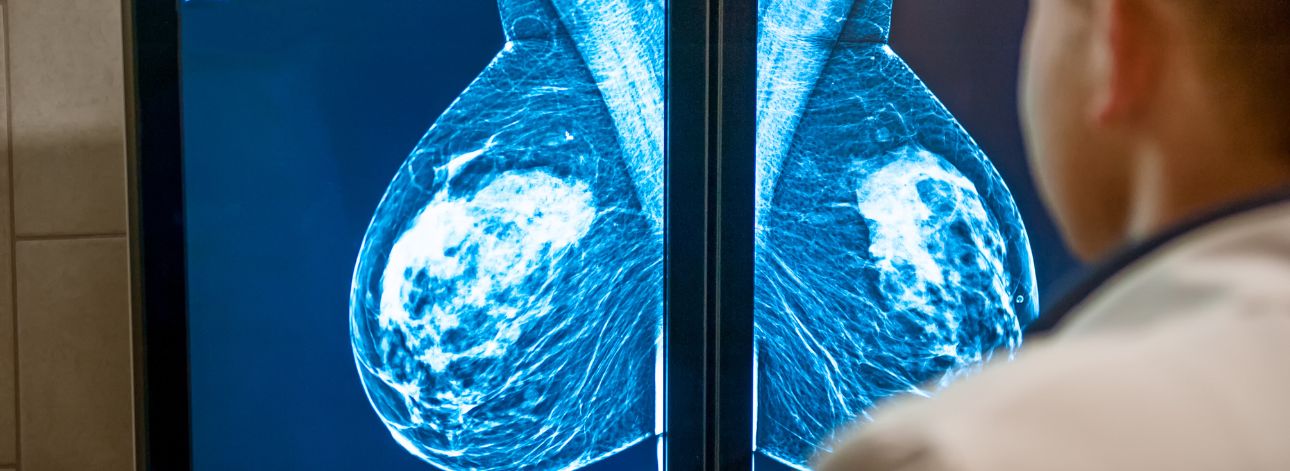

Entenda a mudança da FDA, de idade mínima dos 50 para os 40 anos na realização da mamografia nos Estados Unidos.

Exames de Imagem são essenciais para que médicos vejam o interior do corpo humano sem um procedimento cirúrgico.

O Câncer de Mama é o resultado de uma disfunção celular que faz partes das células crescerem e se multiplicarem sem ordem, formando um tumor.

O autocuidado previne o câncer de mama, pois é um conjunto de ações que ajudam as mulheres na conquista da autonomia e qualidade de vida.

O medicamento contra o câncer de mama, trastuzumabe entansina, ou TDMI-1, agora será distribuído pelo SUS.

O Outubro Rosa é um movimento mundial que reforça a importância da prevenção contra o câncer de Mamas, especialmente as mulheres.

Um tumor é identificado quando há um aumento de volume em partes do corpo. Ele é caracterizado pelo crescimento anormal do número de células, chamadas neoplasias, elas podem ser benignas ou malignas.